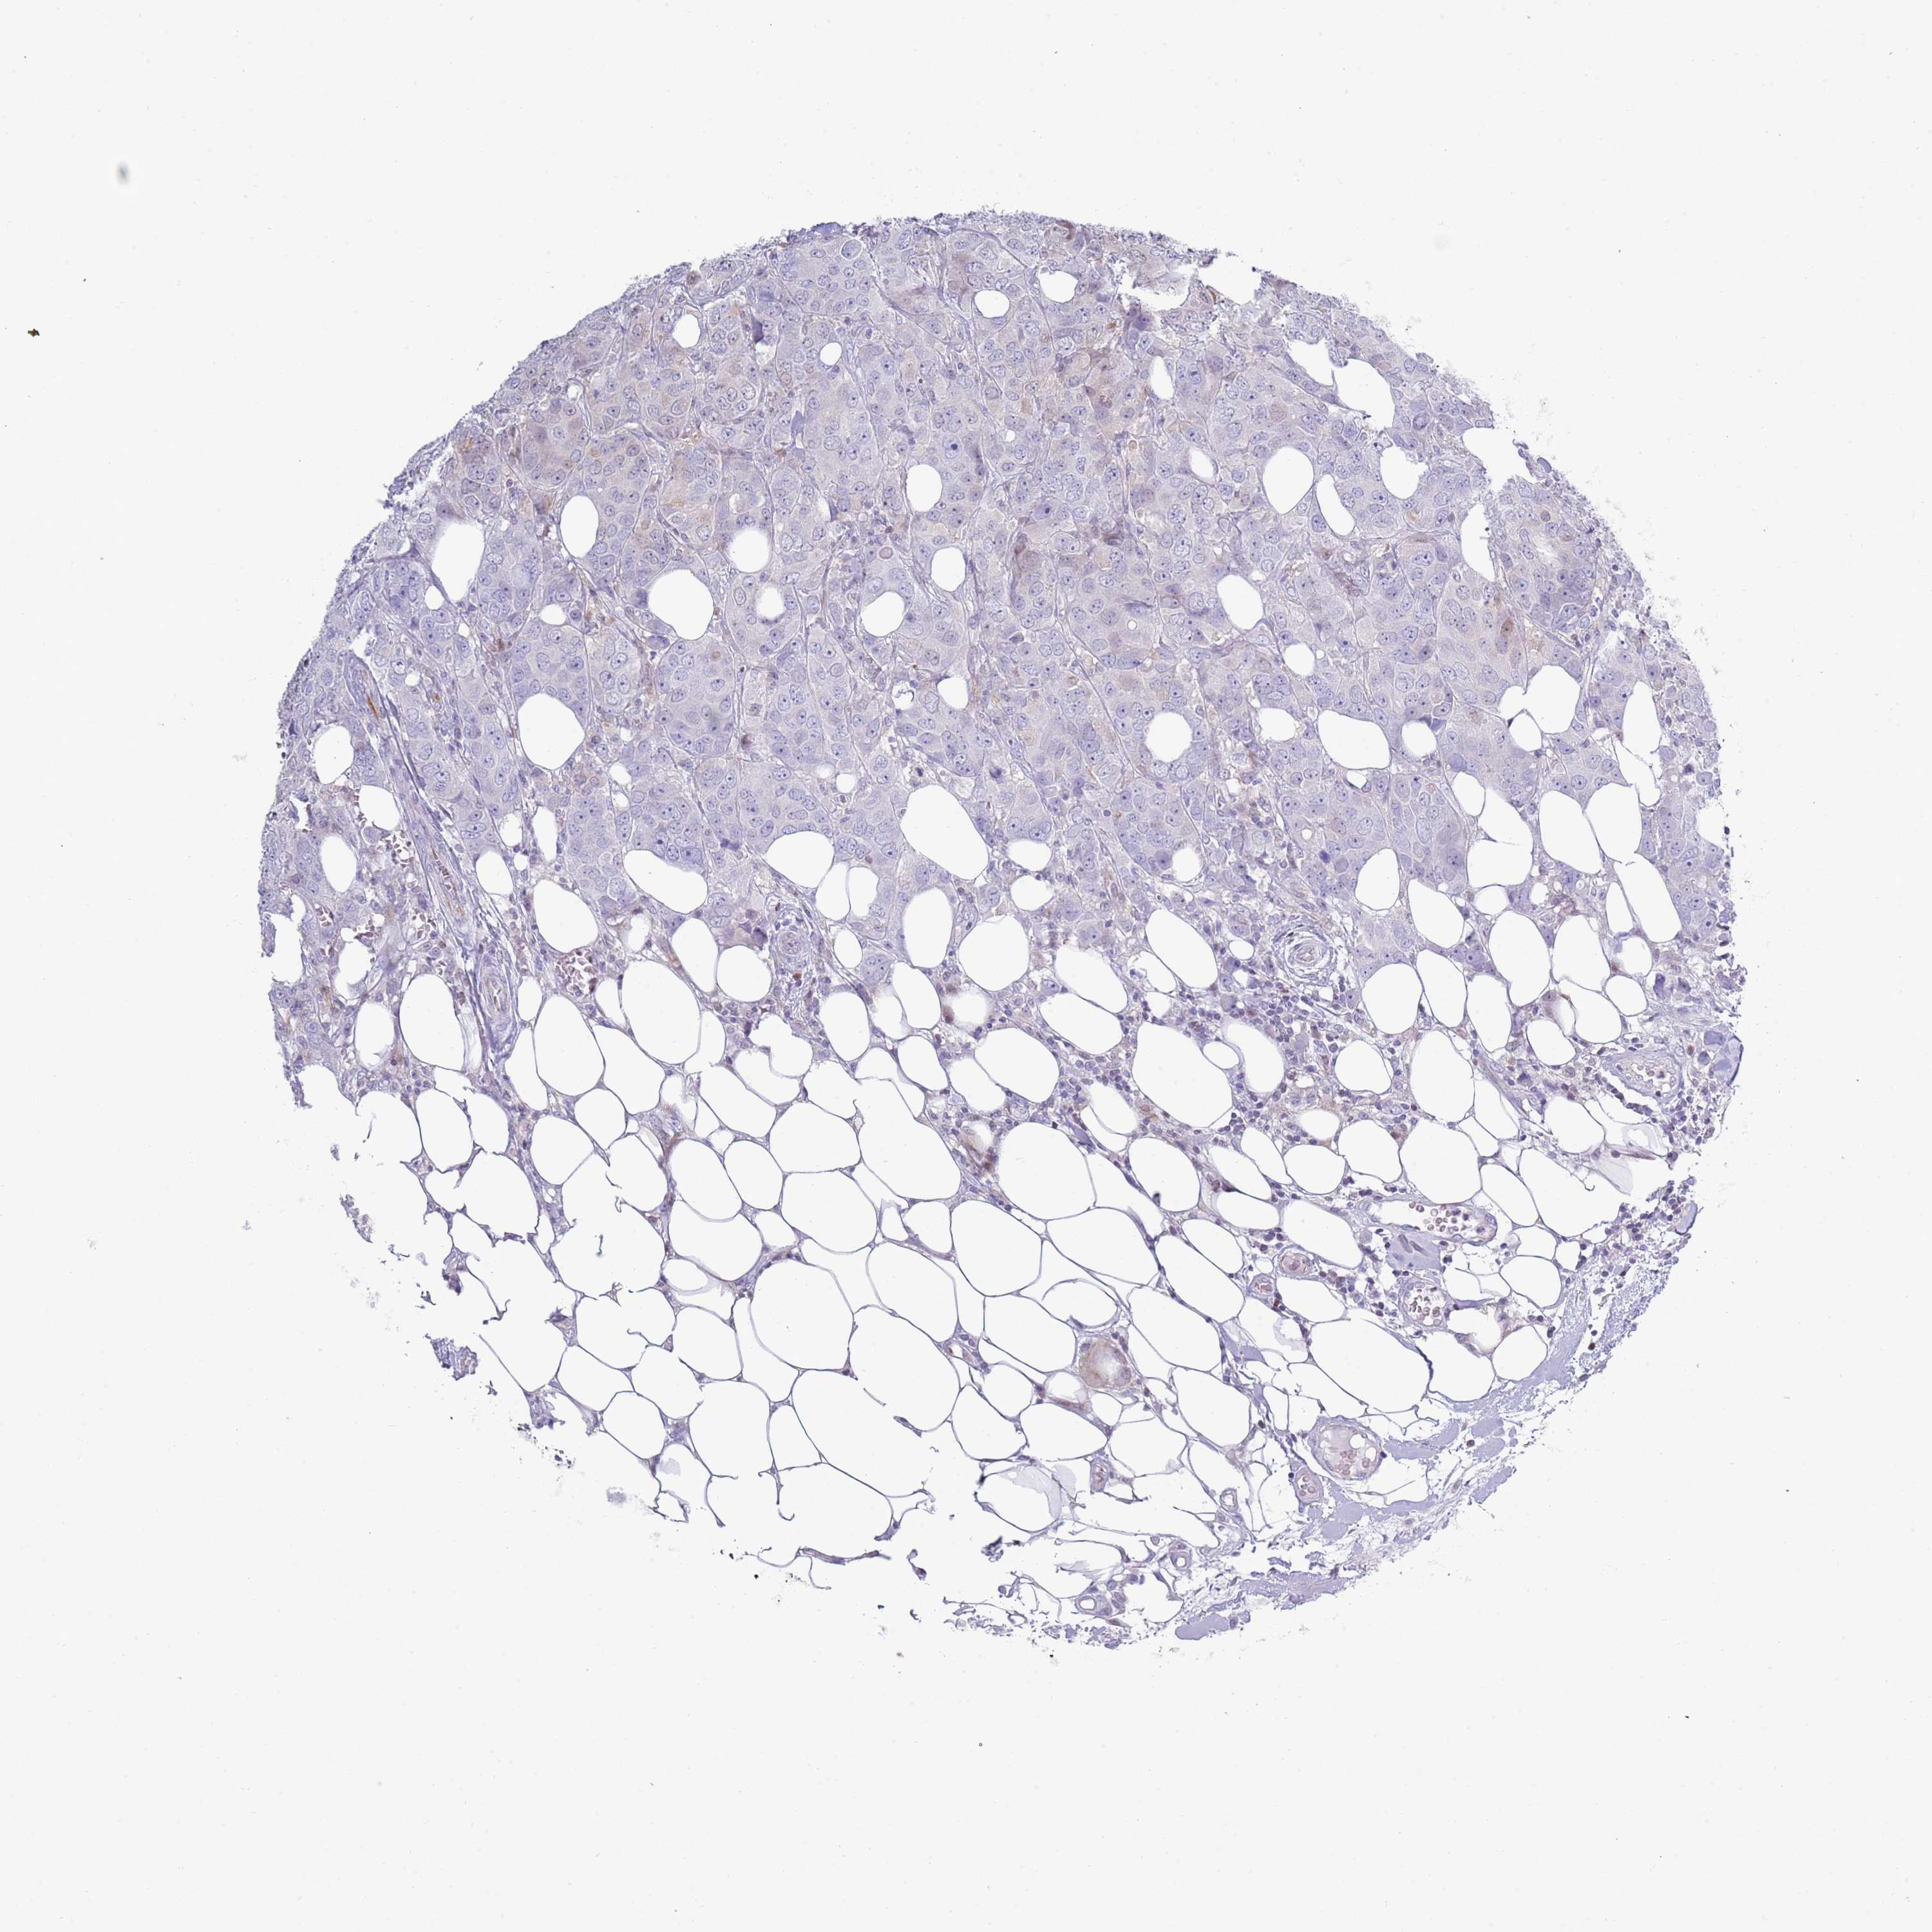

CANCER BREAST CANCER Show tissue menu

BRCA TCGA BRCA VALIDATION PROTEIN EXPRESSION